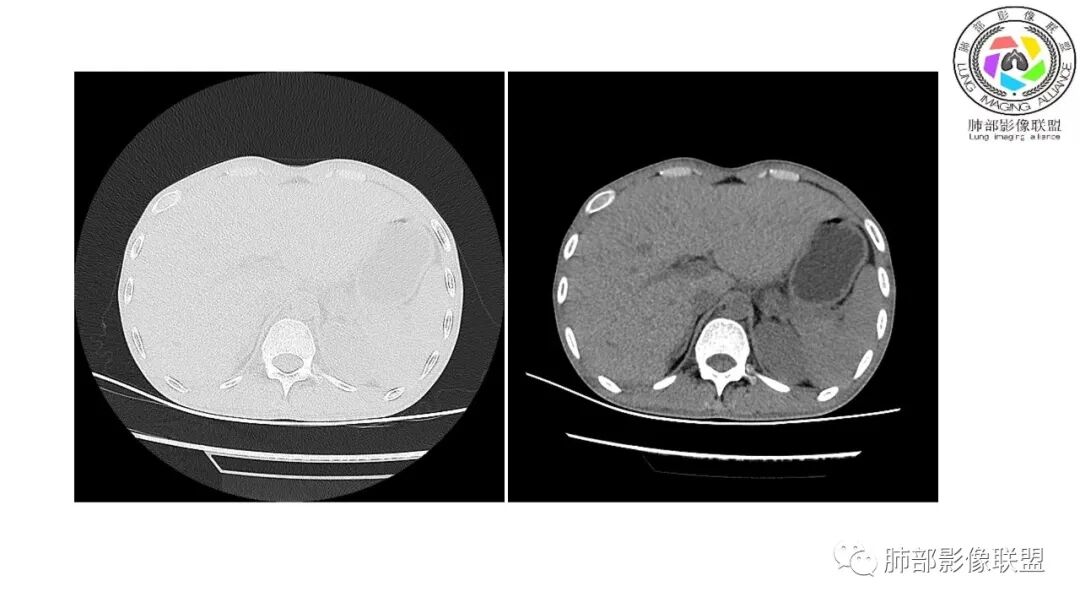

以下为2021-7-15日上腹部CT

影像与临床:1.青年男性,HlV阳性,颜面部皮疹(未提供皮疹图像)、发热(高热),实验室CRP、PCT高,T-Spot阴性。2.右肺下叶空洞结节,壁厚不均,边界清楚,其内线状影,未见液平及钙化,未见卫星灶,纵隔淋巴结增大,双侧腋窝见增大淋巴结。心腔内低密度提示贫血可能。肝脾影增大,未见结节影及块影。腹膜后见多发增大淋巴结。

综合分析:本例肺部影像学改变并不具有特征性,空洞性病灶须与多种疾病鉴别,但年轻HIV阳性患者,高热,皮疹,肝脾增大,纵隔、腋窝、腹膜后见多发增大淋巴结等都强烈提示马尔尼菲篮状菌感染的可能性。